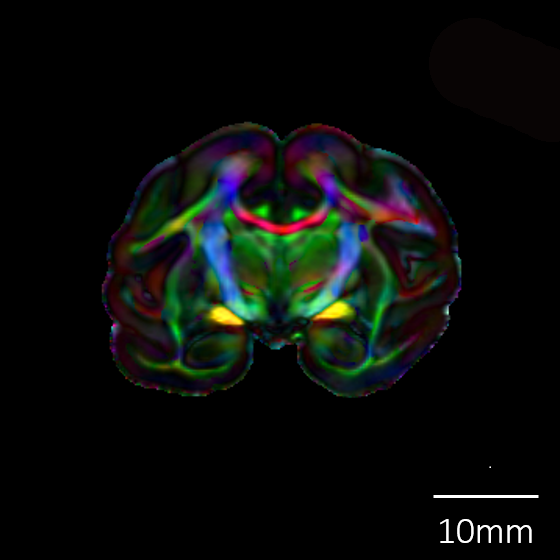

カラーマップ |

![]() |